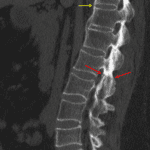

- Acute nondisplaced fracture through the right L2 lamina and pars interarticularis

- Acute nondisplaced fracture through an anterior bridging syndesmophyte at T11-T12

- Bridging anterior syndesmophytes at the thoracolumbar junction. Multilevel osseous fusion of the posterior elements

- Acute nondisplaced fractures in patient with ankylosing spondylitis

Acute nondisplaced fractures through the right L2 lamina and pars interarticularis and through an anterior bridging syndesmophyte at T11-T12 in this patient with multilevel spinal fusion related to ankylosing spondylitis.

No traumatic malalignment.